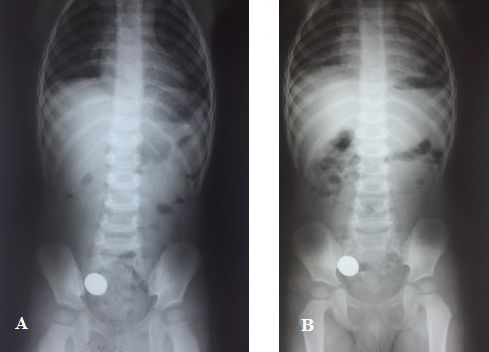

Survey X-ray of abdominal organs (06.11.2018): no free gas identified. Gas air bubble of the stomach of large dimension with a horizontal level of fluid. Enhanced pneumatization of the intestine in the upper abdomen, moderate pneumatization in lower parts. On the right in the projection of pelvis (in projection of ileocecal angle) a foreign body was seen of metal density, round shape with sharp contours, 2.1 cm in diameter (Fi-gure 1A).

Fig. 1. Survey X-ray of abdominal cavity of child H., 2 years 10 months of age on admission to hospital (A), a day after (B):on the right of the iliac region a foreign body (a coin) is determined

Survey X-ray of abdominal organs (07.11.2018): no free gas and fluid levels were determined. The foreign body did not change its position in dynamics, localization was the same. Pneumatization of the intestine was moderately increased in the upper intestine and was moderate in the lower part (Fi-gure 1B).